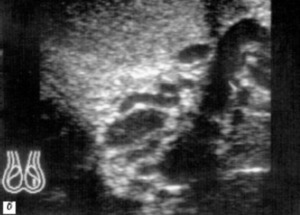

Субклиническое варикоцеле: вены яичка не обнаруживаются путем пальпации, обнаружить варикоцеле можно только на основании результатов УЗИ.

После проведения эндоваскулярной эмболии пациент может покинуть медицинское учреждение уже на следующий день. В амбулаторном порядке осуществляются диагностические процедуры, позволяющие установить эффективность проведенной операции. К ним относят УЗИ-мониторинг, сдачу спермограммы и профилактический осмотр.